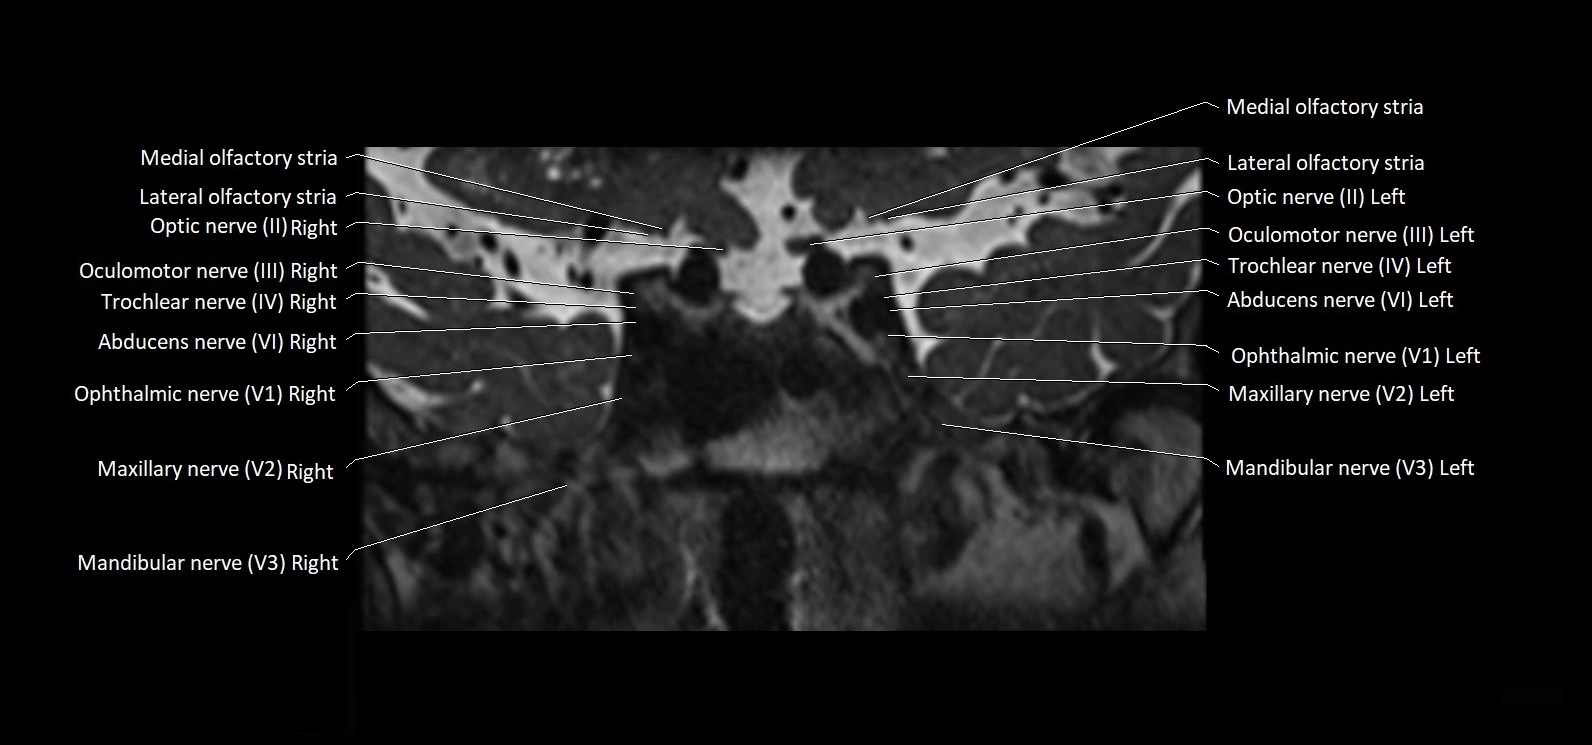

MRI Appearance

• The abducens nerve is a small, thin, linear structure

• Best visualized on high-resolution T2-weighted 3D MRI sequences (e.g., FIESTA or CISS)

• Seen as a hypointense (dark) line running from the brainstem at the pontomedullary junction, traversing the prepontine cistern, and entering Dorello’s canal under the petrosphenoidal ligament, then into the cavernous sinus, and finally the orbit

• May be challenging to visualize in standard MRI due to its small size

• Pathology may be inferred by absence, displacement, or enhancement of the nerve